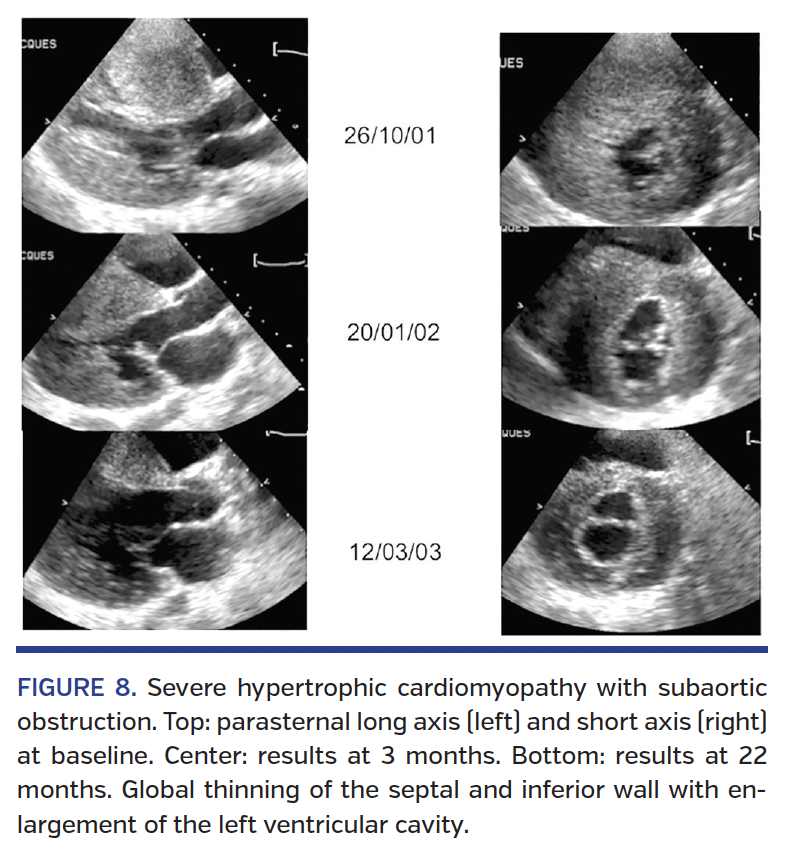

Long-term clinical outcomes. ASA has been associated with very promising long-term outcomes over the past few years (Figures 7 and 8). At our center, survival at 5 and 10 years was 94.1% and 86.9%, respectively, in a series of 240 patients with a mean age of 57 years. This represents a 1.3% mortality rate per year, which is comparable to that of the general French population matched for age and gender (Figure 9).10 The

only predictor of mortality after ASA in our cohort was septum thickness (odds ratio, 1.17 per mm; P=.01). In comparison, in a recent study involving 470 patients with a mean age of 56 years, Jensen et al13 reported an 88% survival rate at 10 years (1.2% mortality per year, also comparable to that of the general population).